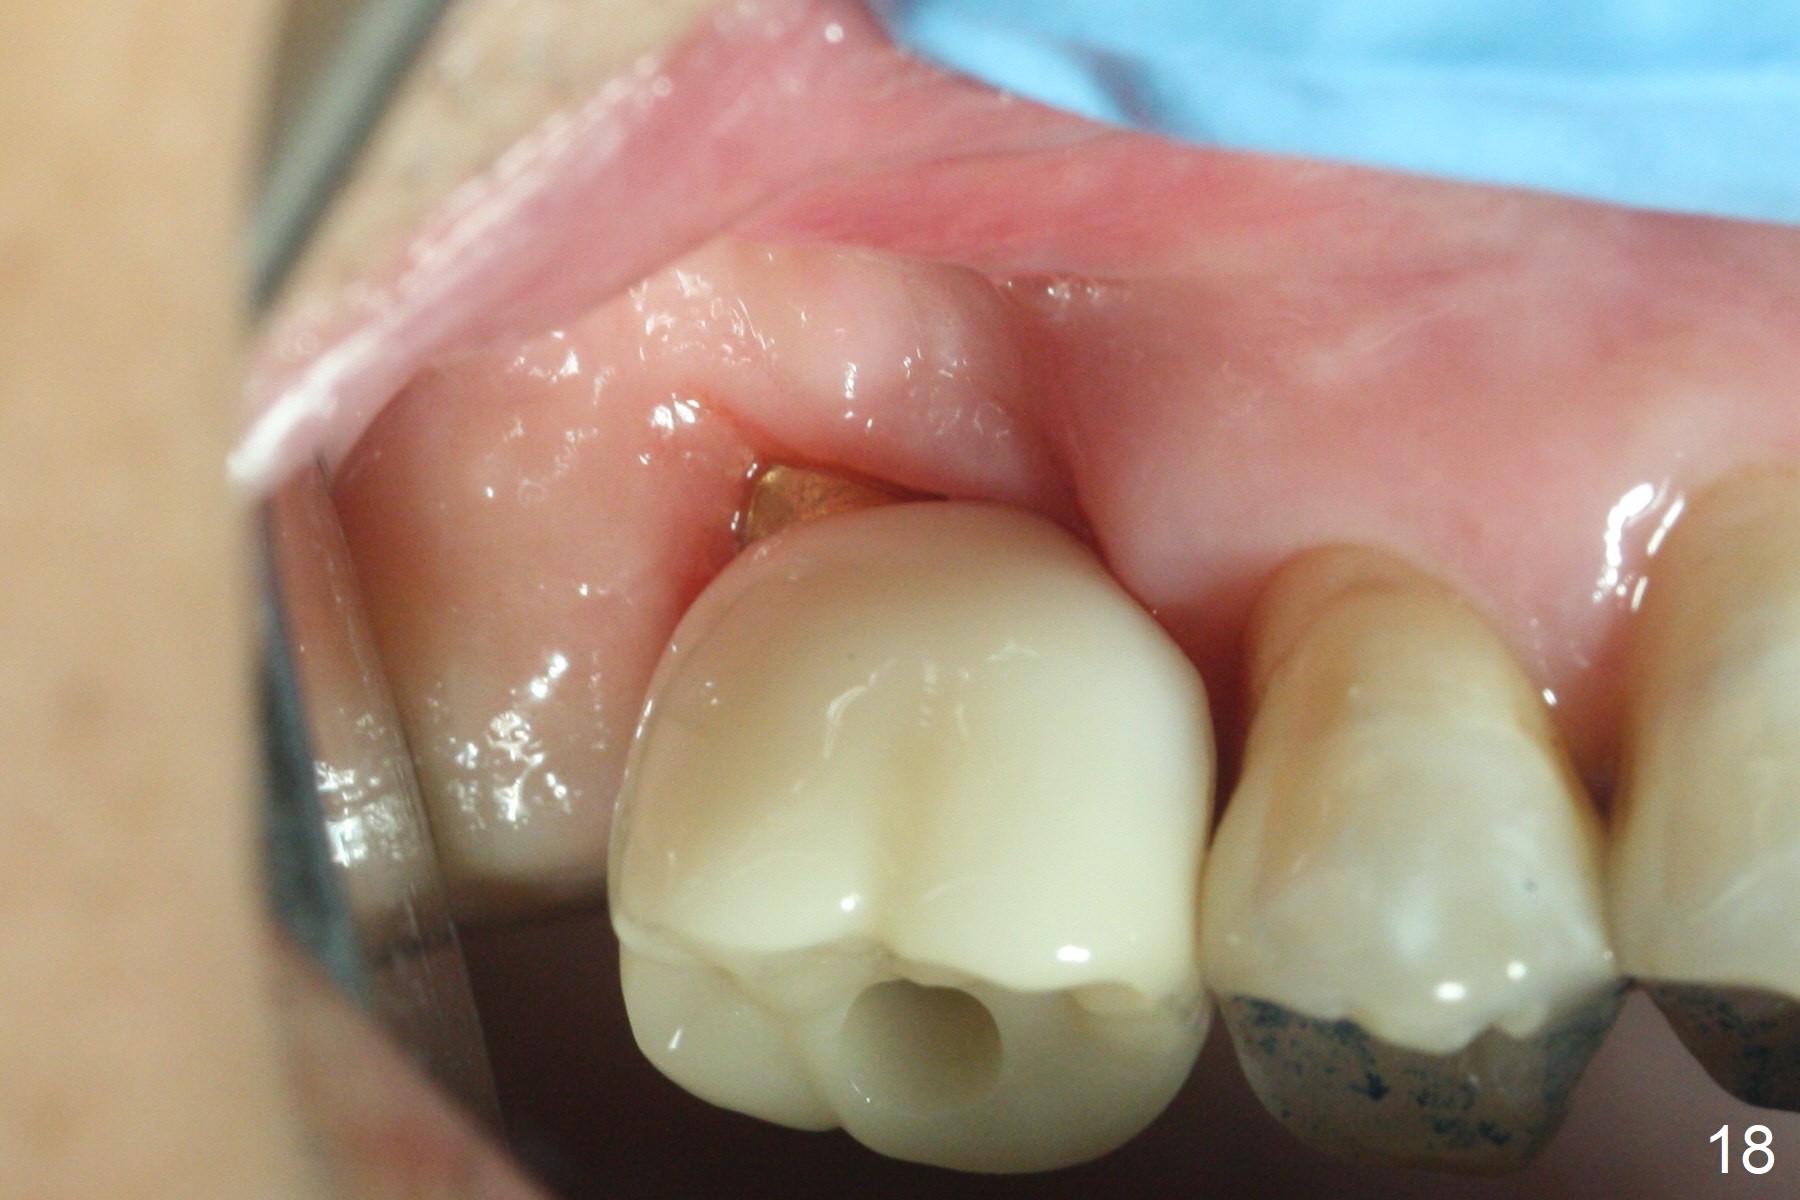

Two weeks later, the buccal gingiva appears to have grown downward (Fig.13). Fig.14 is taken when the provisional is removed. To facilitate this process, change abutment from 4.8x7(3) to (4.5) mm and a new provisional is fabricated (Fig.15): note the metal exposure distobuccally. When the patient returns in another two week, the gap should be able to disappear. There is no loss of bone graft 3 months postop (Fig.16). Two weeks later (3.5 months postop), the margin of the abutment is supragingival buccally and subgingival palatally (Fig.17,18). The gingiva seems to have migrated downward (Fig.19 arrow), while the bone density around the coronal implant appears to increase 5.5 months post cementation (Fig.20). There is buccal swelling with purulent discharge 1.5 years post cementation (Fig.21). Perimplantitis develops. Tuberosis bone graft will be performed when the limited ortho is finished.